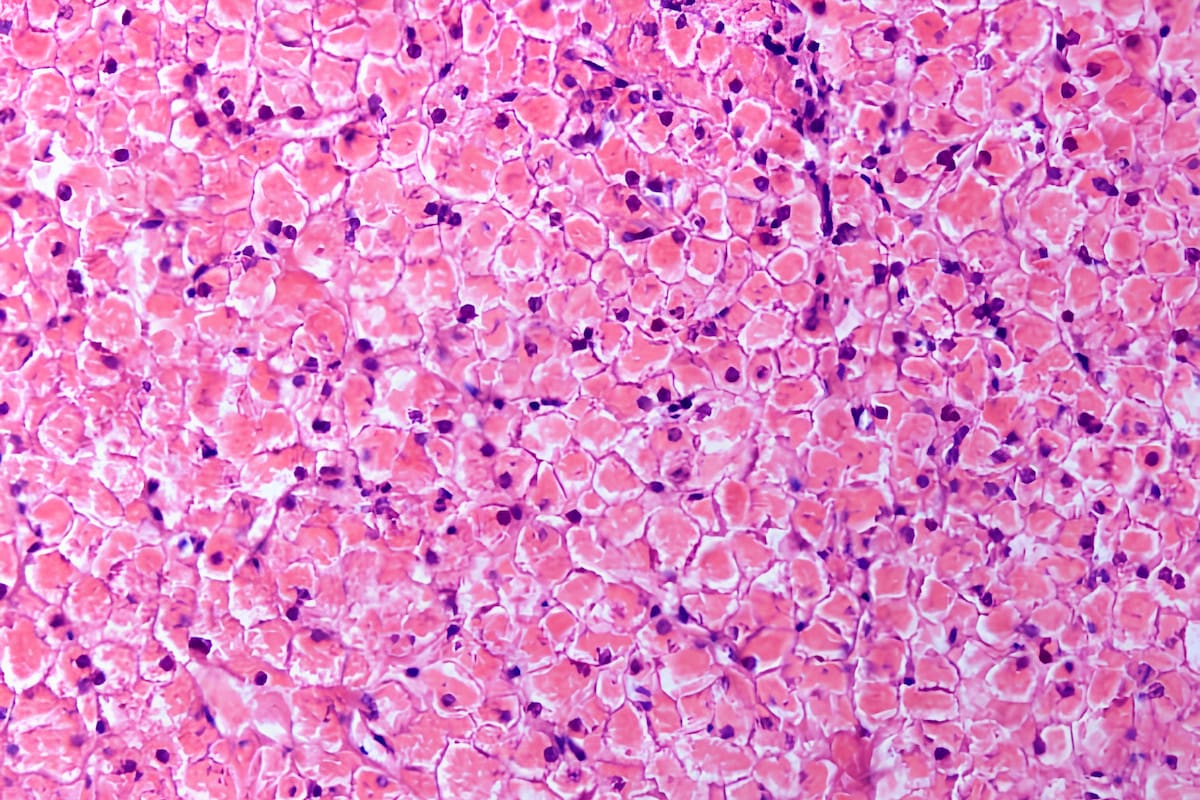

La enfermedad de Pompe genera una acumulación anormal de glucógeno.

Dicha deficiencia enzimática conlleva a una acumulación de glucógeno en las células y tejidos musculares, si bien el glucógeno es una forma de almacenamiento de carbohidratos que se convierte en glucosa cuando el cuerpo requiere energía.